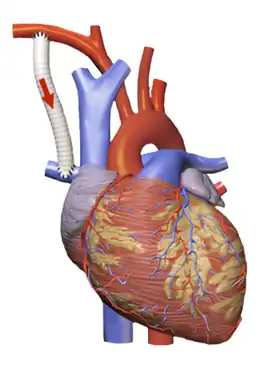

Modified Blalock–Taussig Shunt connecting right subclavian artery to pulmonary artery | |

Alternatives

While the originally described Blalock–Taussig shunt directly connected the subclavian and pulmonary arteries, in contemporary practice a modified version of the procedure is more commonly used.[3] In the modified Blalock–Taussig shunt a length of artificial tubing typically made from PTFE (Gore-tex) is sewn between either the subclavian or the carotid artery and the corresponding side branch of the pulmonary artery.[3] This modification removes the need to cut off blood supply and makes it easier to regulate the blood flow to the lungs. Some centers now use a shunt directly from the right ventricle to the pulmonary artery, a Sano shunt. This is done to avoid the reduced diastolic blood flow in the coronary circulation associated with the Blalock–Taussig shunt.